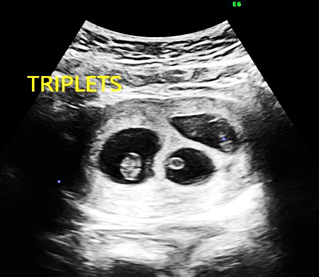

A multiple pregnancy is one in which the mother carries more than one baby in her womb. Most commonly is it two called as twins. If there are three, it is called as triplet and if four, it is quadruplet pregnancy..

• Early viability scan- this scan is to determine the number of fetuses and type of multiple pregnancy, that is to determine the CHORIONICITY.

• First trimester screening- at 11-13+6weeks- Here, we determine the number of fetuses, type of multiple pregnancy, dating, structural abnormalities and screen for chromosomal abnormalities.